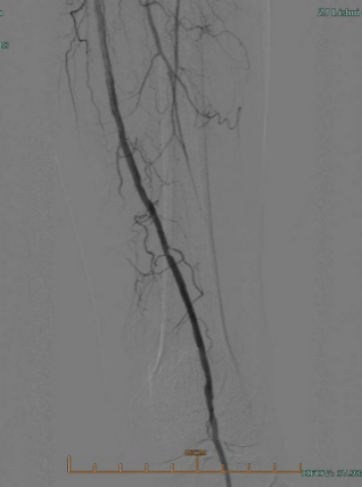

★ 造影评估

右侧股动脉翻山入路,经鞘管造影显示下肢动脉多发硬化改变。

左侧股浅动脉中下段局部重度钙化狭窄闭塞,左股浅动脉下段,腘动脉局部中度钙化狭窄。

股浅动脉

腘动脉

★ 管腔准备

导管配合V-18 control wire通过病变段到达远端胫前动脉,交换V-14 control wire,引入Shockwave IVL M5(5.0×60mm)。冲击波球囊低压慢扩左侧腘动脉、股浅动脉下段钙化病变段(将球囊充盈至4atm后,激发震波,在完成一组脉冲后,将球囊缓慢充盈至6atm并持续60秒)

★ 术后造影

病变解除,管腔及血流恢复通畅,未见夹层及造影剂外渗